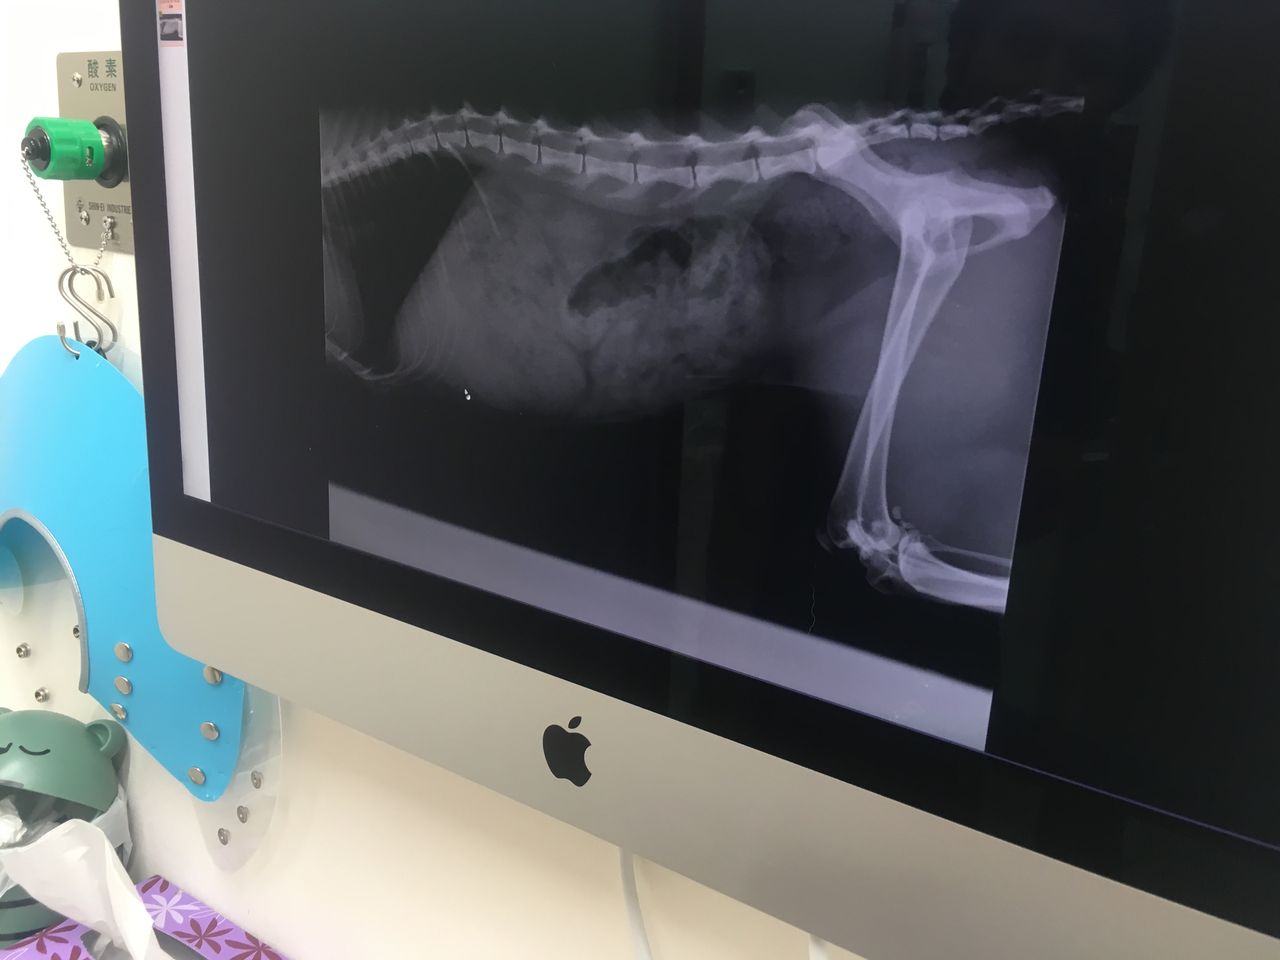

いつもの60kコース沿いに御座います動物病院へ~

エイズと白血病は陰性、

推定1歳~2歳

飼い猫かどうか断言は出来ないものの

人間との関わりがある環境にいた事だけは確か、

と先生は仰せで御座いました。

「外に出る猫や外で生活している猫はエイズの可能性が高いんです」

とも仰せな上

「だいたいエイズの猫は見ると分かります

この子は見てすぐ違うと思いました」

と先生~